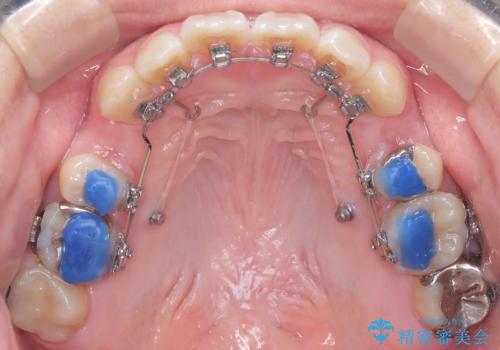

- 口元が出ている(突出している)ことを気にされて来院されました。精密な検査の結果、前歯を大きく後退させるスペースが必要と診断。患者様の**「前歯を下げたい」という強いご要望に応えるため、上下左右の第一小臼歯を抜歯し、そのスペースを利用して前歯を奥へ移動させる治療計画を立案しました。また、人目を気にせず治療できるよう、上顎に裏側矯正、下顎に表側矯正を組み合わせたハーフリンガル矯正**を提案しました。

今回の矯正治療では、前歯を大きく後退させるスペースを確保するため、計画通り上下左右の第一小臼歯を抜歯しました。装置には、上顎には目立たない裏側矯正(舌側矯正)を、下顎には透明な審美ブラケットを使用するハーフリンガル矯正を採用しました。抜歯によってできたスペースを最大限に活用し、前歯を効率よく後方へ移動。治療の結果、口元の突出感が大幅に解消され、Eライン(横顔の美しさの基準)も改善しました。人目を気にすることなく治療を完遂し、自信の持てる美しい横顔を獲得していただけました。